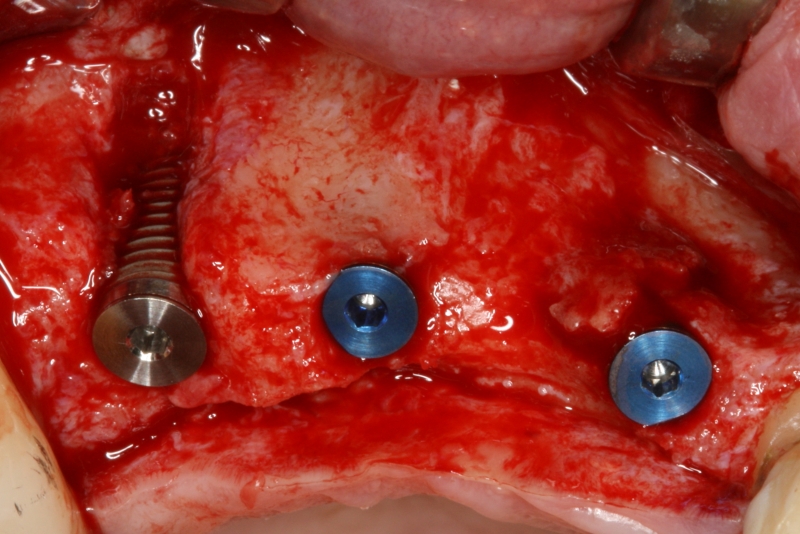

botiss cerabone® & Jason® membrane for GBR - Clinical case by Dr. S. Kovalevsky

Implant insertion in atrophic alveolar ridge